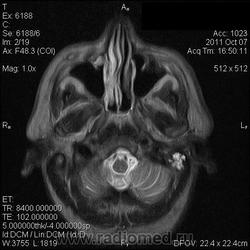

на МРТ - Определяется скопление крови в препонтинной цистерне, в проекции супраселлярной цистерны, в кортикальных бороздах полушарий головного мозга,  в проекции краниоспинального перехода. Выявляется горизонтальный уровень крови в задних рогах боковых желудочков. Боковые, третий желудочки резко расширены. Определяется перивентрикулярное повышение интенсивности сигнала от белого вещества головного мозга. Срединные структуры не смещены. Кортикальные борозды умеренно сглажены. Сильвиев водопровод прослеживается на всем протяжении. Отмечается смещение дна третьего желудочка каудально, с резким уменьшением размеров супраселлярной цистерны; базальные цистерны уменьшены в размере.

В проекции базальной артерии определяется аневризма размером до 4х6 мм.

Helios, Танюша а что конкретно у вас не укладывается между описанием и картинкой? Импульсные последовательности прикольные конечно; кровь выглядит не очень привычно, но это низкопольный Openmark. Какие еще варианы могут быть?

Мне напоминает FLAIR. В желудочках уровни крови и белое по субарахноидальным щелям тоже кровь. Аневризму тоже не вижу. Может долихоэктазия, если смотреть на сагитталы. Мелковато для меня, наверное.

Картинки действительно мелковаты. Я видел весь пакт изображений. Аневризма была хорошо видна на МР-ангиограммах, но Евгений их не выложил; а на обычных сканах ее четко не видно. Почему такие сигнальные характеристики у крови сложно сказать, я думаю, что в большую степень завязано давности кровоизлияния (четко не известно, когда оно произошло), на типе ИП и самом оборудовании... Такие вот мысли...